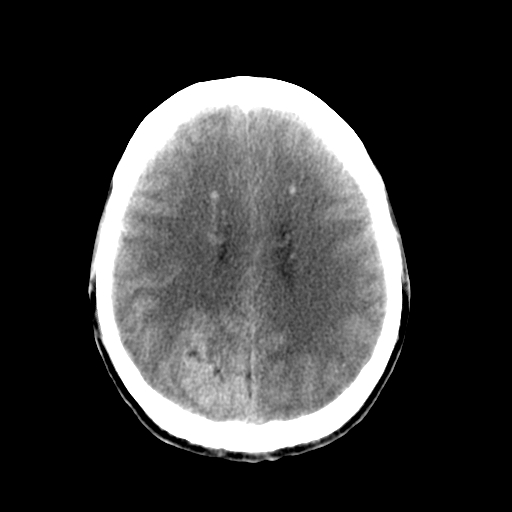

标题: CT17002:M48Y,血管畸形,血管瘤,请鉴赏! [打印本页]

标题: CT17002:M48Y,血管畸形,血管瘤,请鉴赏!

男48y,头痛多年,加重一天!

典型的血管畸形---avm  -----右侧枕顶叶及侧脑室三角区等高混杂密度影夹杂少许低密影显示,无明显水肿,增强可见明显的供血动脉与引流静脉显示